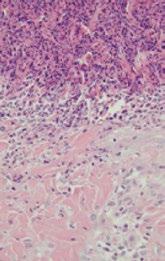

PAN-BR AGRO:

Acadeia produtiva da carne suína brasileira pela posição global que ocupa tanto em volume produzido quanto a extensão de mercados e consumidores que alcança, é constantemente desafiada a sofisticar seus programas de autocontrole e garantia da qualidade.

O espectro de responsabilidade se amplia além da mitigação dos riscos diretos ao consumidor, pelas doenças transmitidas por alimentos, para a dimensão ambiental e comunitária. É neste cenário que está posta a discussão do papel da agropecuária na seleção e disseminação de bactérias resistentes aos antimicrobianos (ATM), que podem atingir o homem pela via alimentar e também pela exposição ao ambiente.

A preocupação se fundamenta no alarmante prognóstico de óbitos relacionados à falta de eficiência dos ATM para as próximas décadas (O’NEILL, 2016).

O uso de ATM na produção animal e vegetal é um fator de risco potencialmente importante para seleção de microrganismos resistentes, disseminação de determinantes de resistência e transmissão para humanos via consumo de alimentos. Assim se cristaliza o conceito da resistência antimicrobiana transmitida por alimentos (Fooborne AMR).